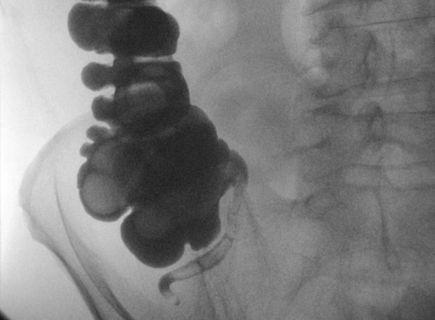

多年来,研究人员一直在寻找阑尾的功能。最主要的假设是,它是一个好肠菌的天堂,并且帮助我们抵挡了一些病毒的感染。 对于这建议最好的证据之一是这项2012年的研究,这研究发现了在没阑尾的情况下出现艰难梭状芽孢杆菌(Clostridium difficile)肠炎的复发率高于普通人的四倍。这种细菌感染会引起腹泻,发热,恶心,和腹痛。

科学美国人 (Scientific American)解释说,在纽约温思罗普(Winthrop)大学医院所报的病例中,有着阑尾的复发率是11%,但没有阑尾的复发率是高于48%。